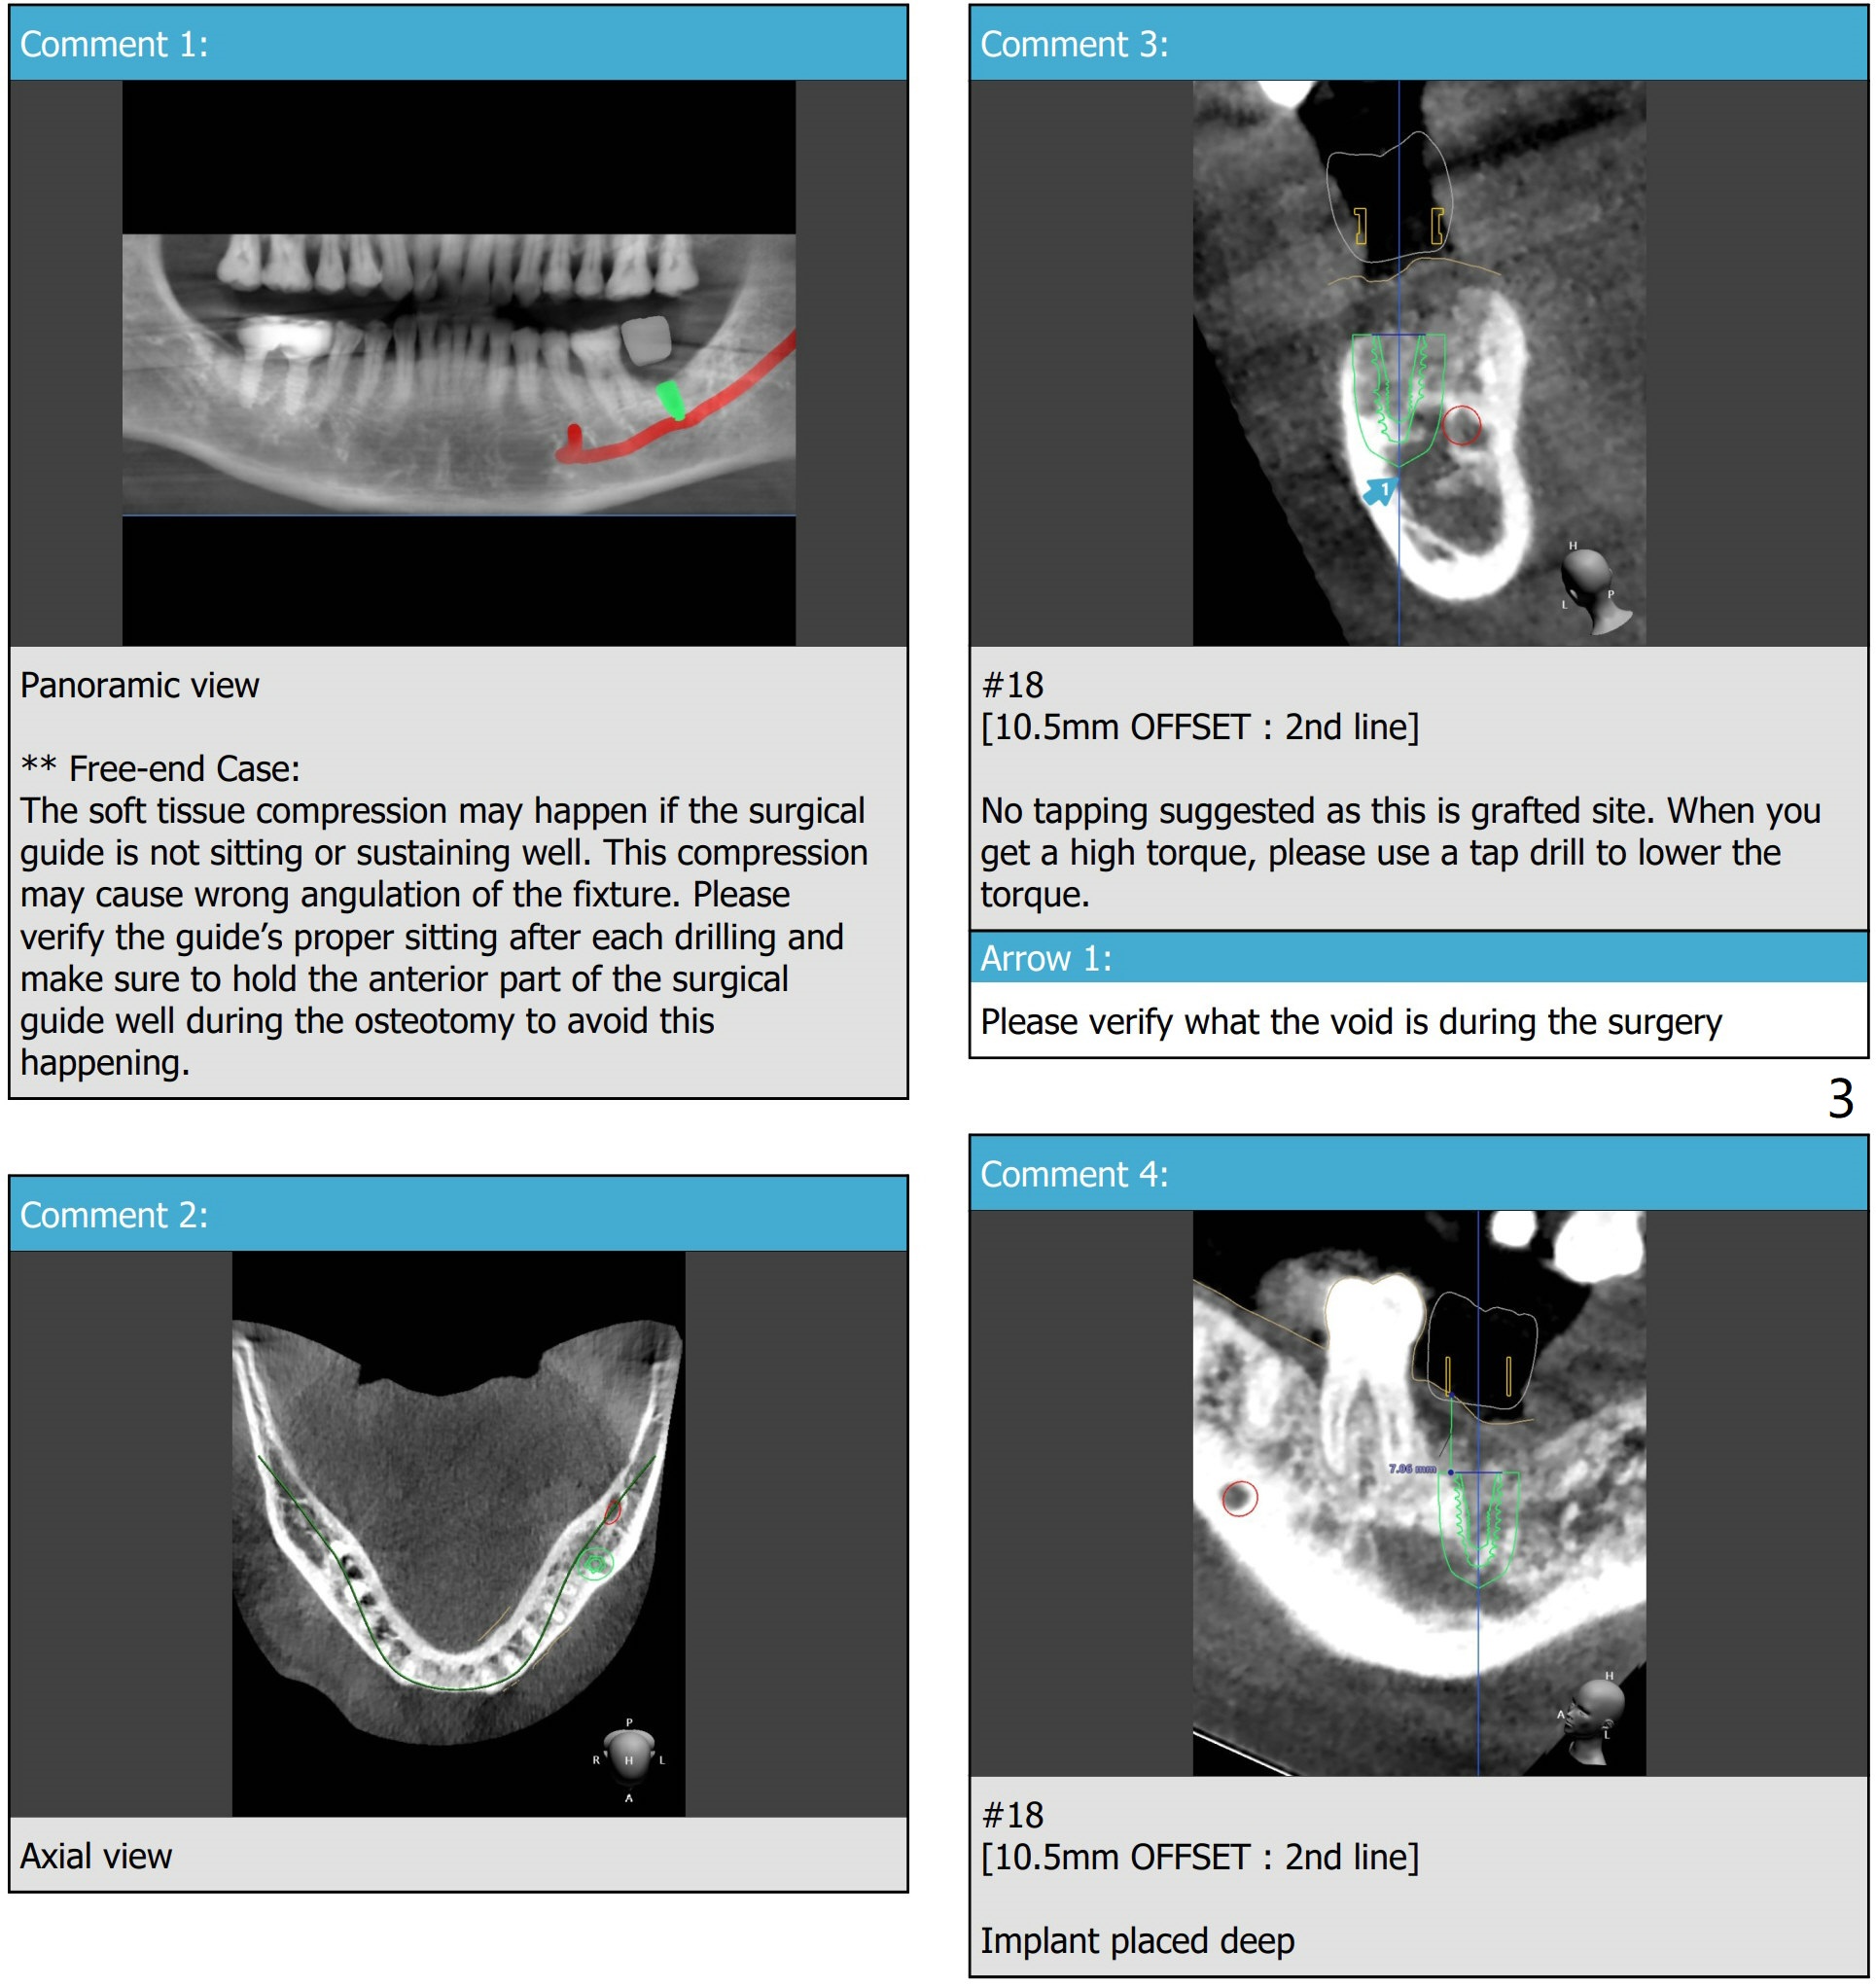

Narrow Fixture Bypasses Nerve

Prepare 4 mm Biopsy punch and 4-0 Plain Gut suture. Save the autogenous bone for regraft, especially buccal.